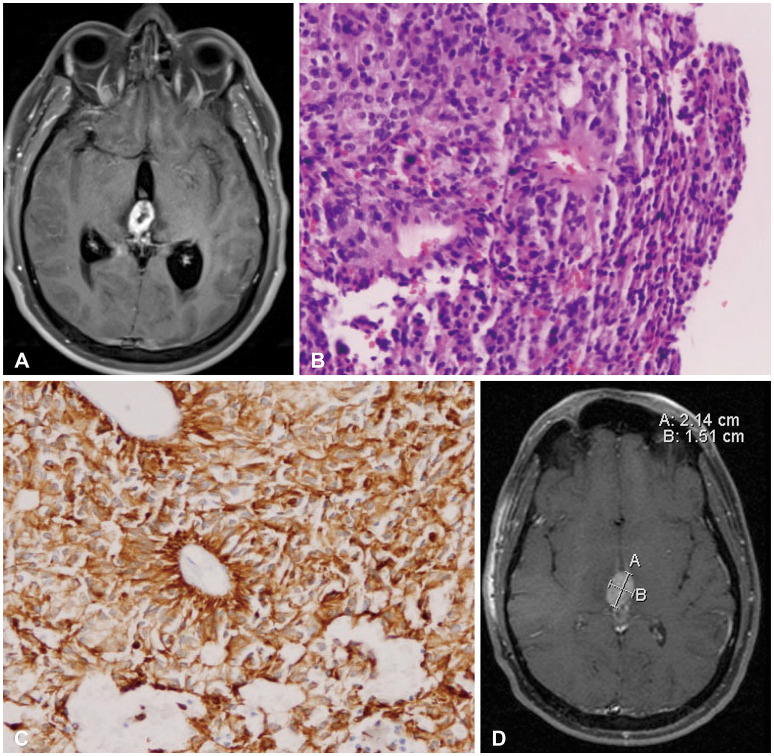

Abstract Image